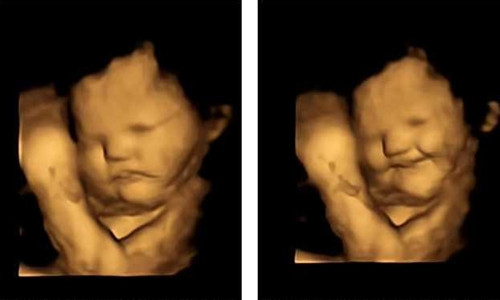

| Ảnh siêu âm 4D chứng minh thai nhi đã có khẩu vị ngay từ trong bụng mẹ. |

Kết quả cho thấy chỉ cần một lượng nhỏ bột cà rốt hoặc cải xoăn cũng có thể kích thích phản ứng vị giác của thai nhi. Khi phụ nữ mang thai ăn cà rốt, thai nhi thường biểu hiện khuôn mặt tươi cười trên ảnh chụp quét, nhưng khi phụ nữ mang thai chuyển sang cải xoăn, thai nhi lại có xu hướng biểu hiện khuôn mặt không thích chút nào, thậm chí cau có khó chịu, có trẻ còn quẫy đạp mạnh mẽ.